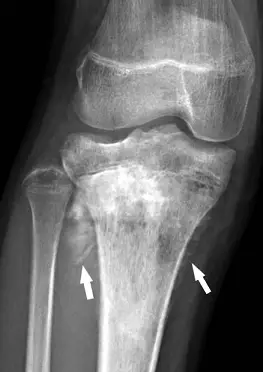

附圖是一位13歲女性脛骨骨肉瘤(osteosarcoma)的膝部X光影像,箭頭所指的影像表現是下列何者?

骨肉瘤(osteosarcoma)在X光影像常見的典型表現為侵蝕性骨破壞合併多種積極型骨膜反應(aggressive periosteal reaction),其中最具特徵性的包括放射狀新骨增生(sunburst pattern)及Codman’s triangle。

從附圖的膝部前後投射平片可見,在脛骨近端外側皮質明顯被破壞,同時皮質外緣向外彈性撐開並生成多道細長放射狀骨痂,呈放射狀或毛髮狀(hair-on-end)排列(白色箭頭所指)。這些細長骨痂與骨幹成銳角並可延伸至軟組織邊緣,無明顯關節腔內游離體或典型軟組織鈣化的團塊狀鈣化。整體病灶呈混合性滲透性破壞,邊界模糊,符合高度惡性骨腫瘤的X光所見。